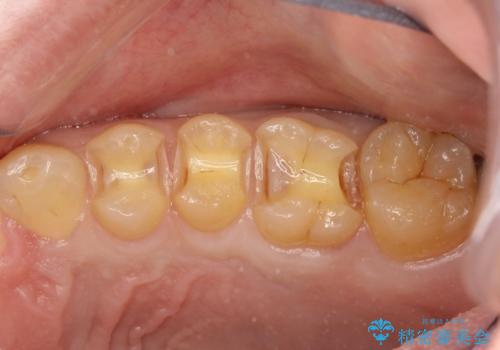

- 虫歯の治療を希望されて来院された患者様です。

歯と歯の間の虫歯が多く、同じブロックの歯をまとめて治療していくこととしました。

今回、幸いにもそんなに大きな虫歯がなかったため、虫歯をとって、セラミックインレーにて修復することが来ました。